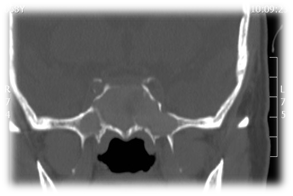

The commonest pathogens include Staphylococcus aureus, aerobic Gram-negative bacilli and anaerobes.10-14 These patients presented with headache, rhinorrhea, nasal obstruction, and blurred vision. The most common presenting symptom of sphenoid sinus disease is mainly headache. In the majority of previous reports, headache was nonspesific in location, quality and intensity.15 Physical examination and endoscopic finding may show mucopurulent secretion at the sphenoethmoidal area, edema of the sphenoethmoidal recess mucosa and polypoid tissue in the sphenoethmoidal recess. In CT scan of the sinuses (Figure 1) will show opacification in the sphenoid sinus, with mucosal wall thickening and air-fluid level. Management of these patients is medical treatment with antibiotic based on culture with topical corticosteroid and decongestant, the surgical intervention (endoscopic sphenoidotomy) (Figure 2) if failed medical treatment or patient presented with complications.

Figure 1 CT scans sinuses with homogenous opacification of both sphenoid sinuses.